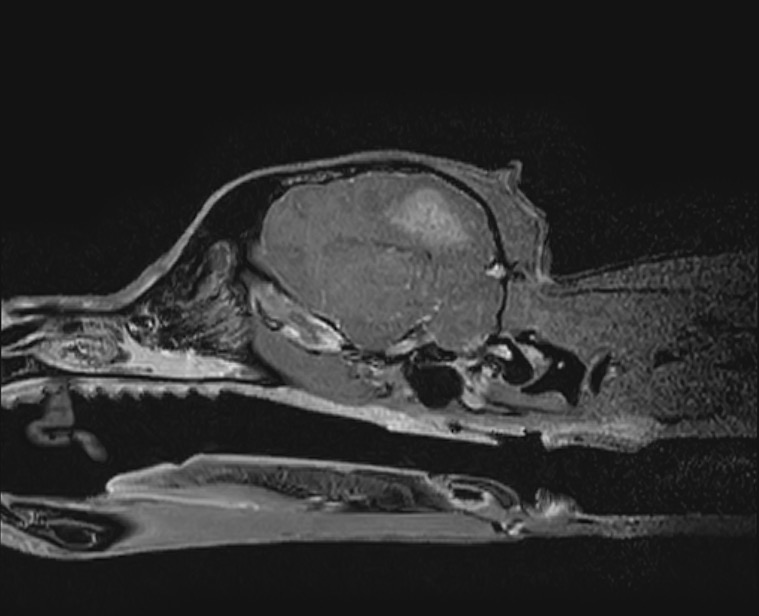

治療開始2週間後に実施した頭部MRI再検査では、脳の浮腫といった脳圧亢進所見、大脳後頭葉領域の炎症所見がすべて改善し、 わんちゃん自身もふらつきや眼振は無くなり、元気や食欲といった一般状態も極めて良好でした。

脳炎は治療をストップすると再発する恐れがあるため現在も治療継続中ではありますが、

早期診断→早期治療を行えたため、現在も良好な経過をたどっています。